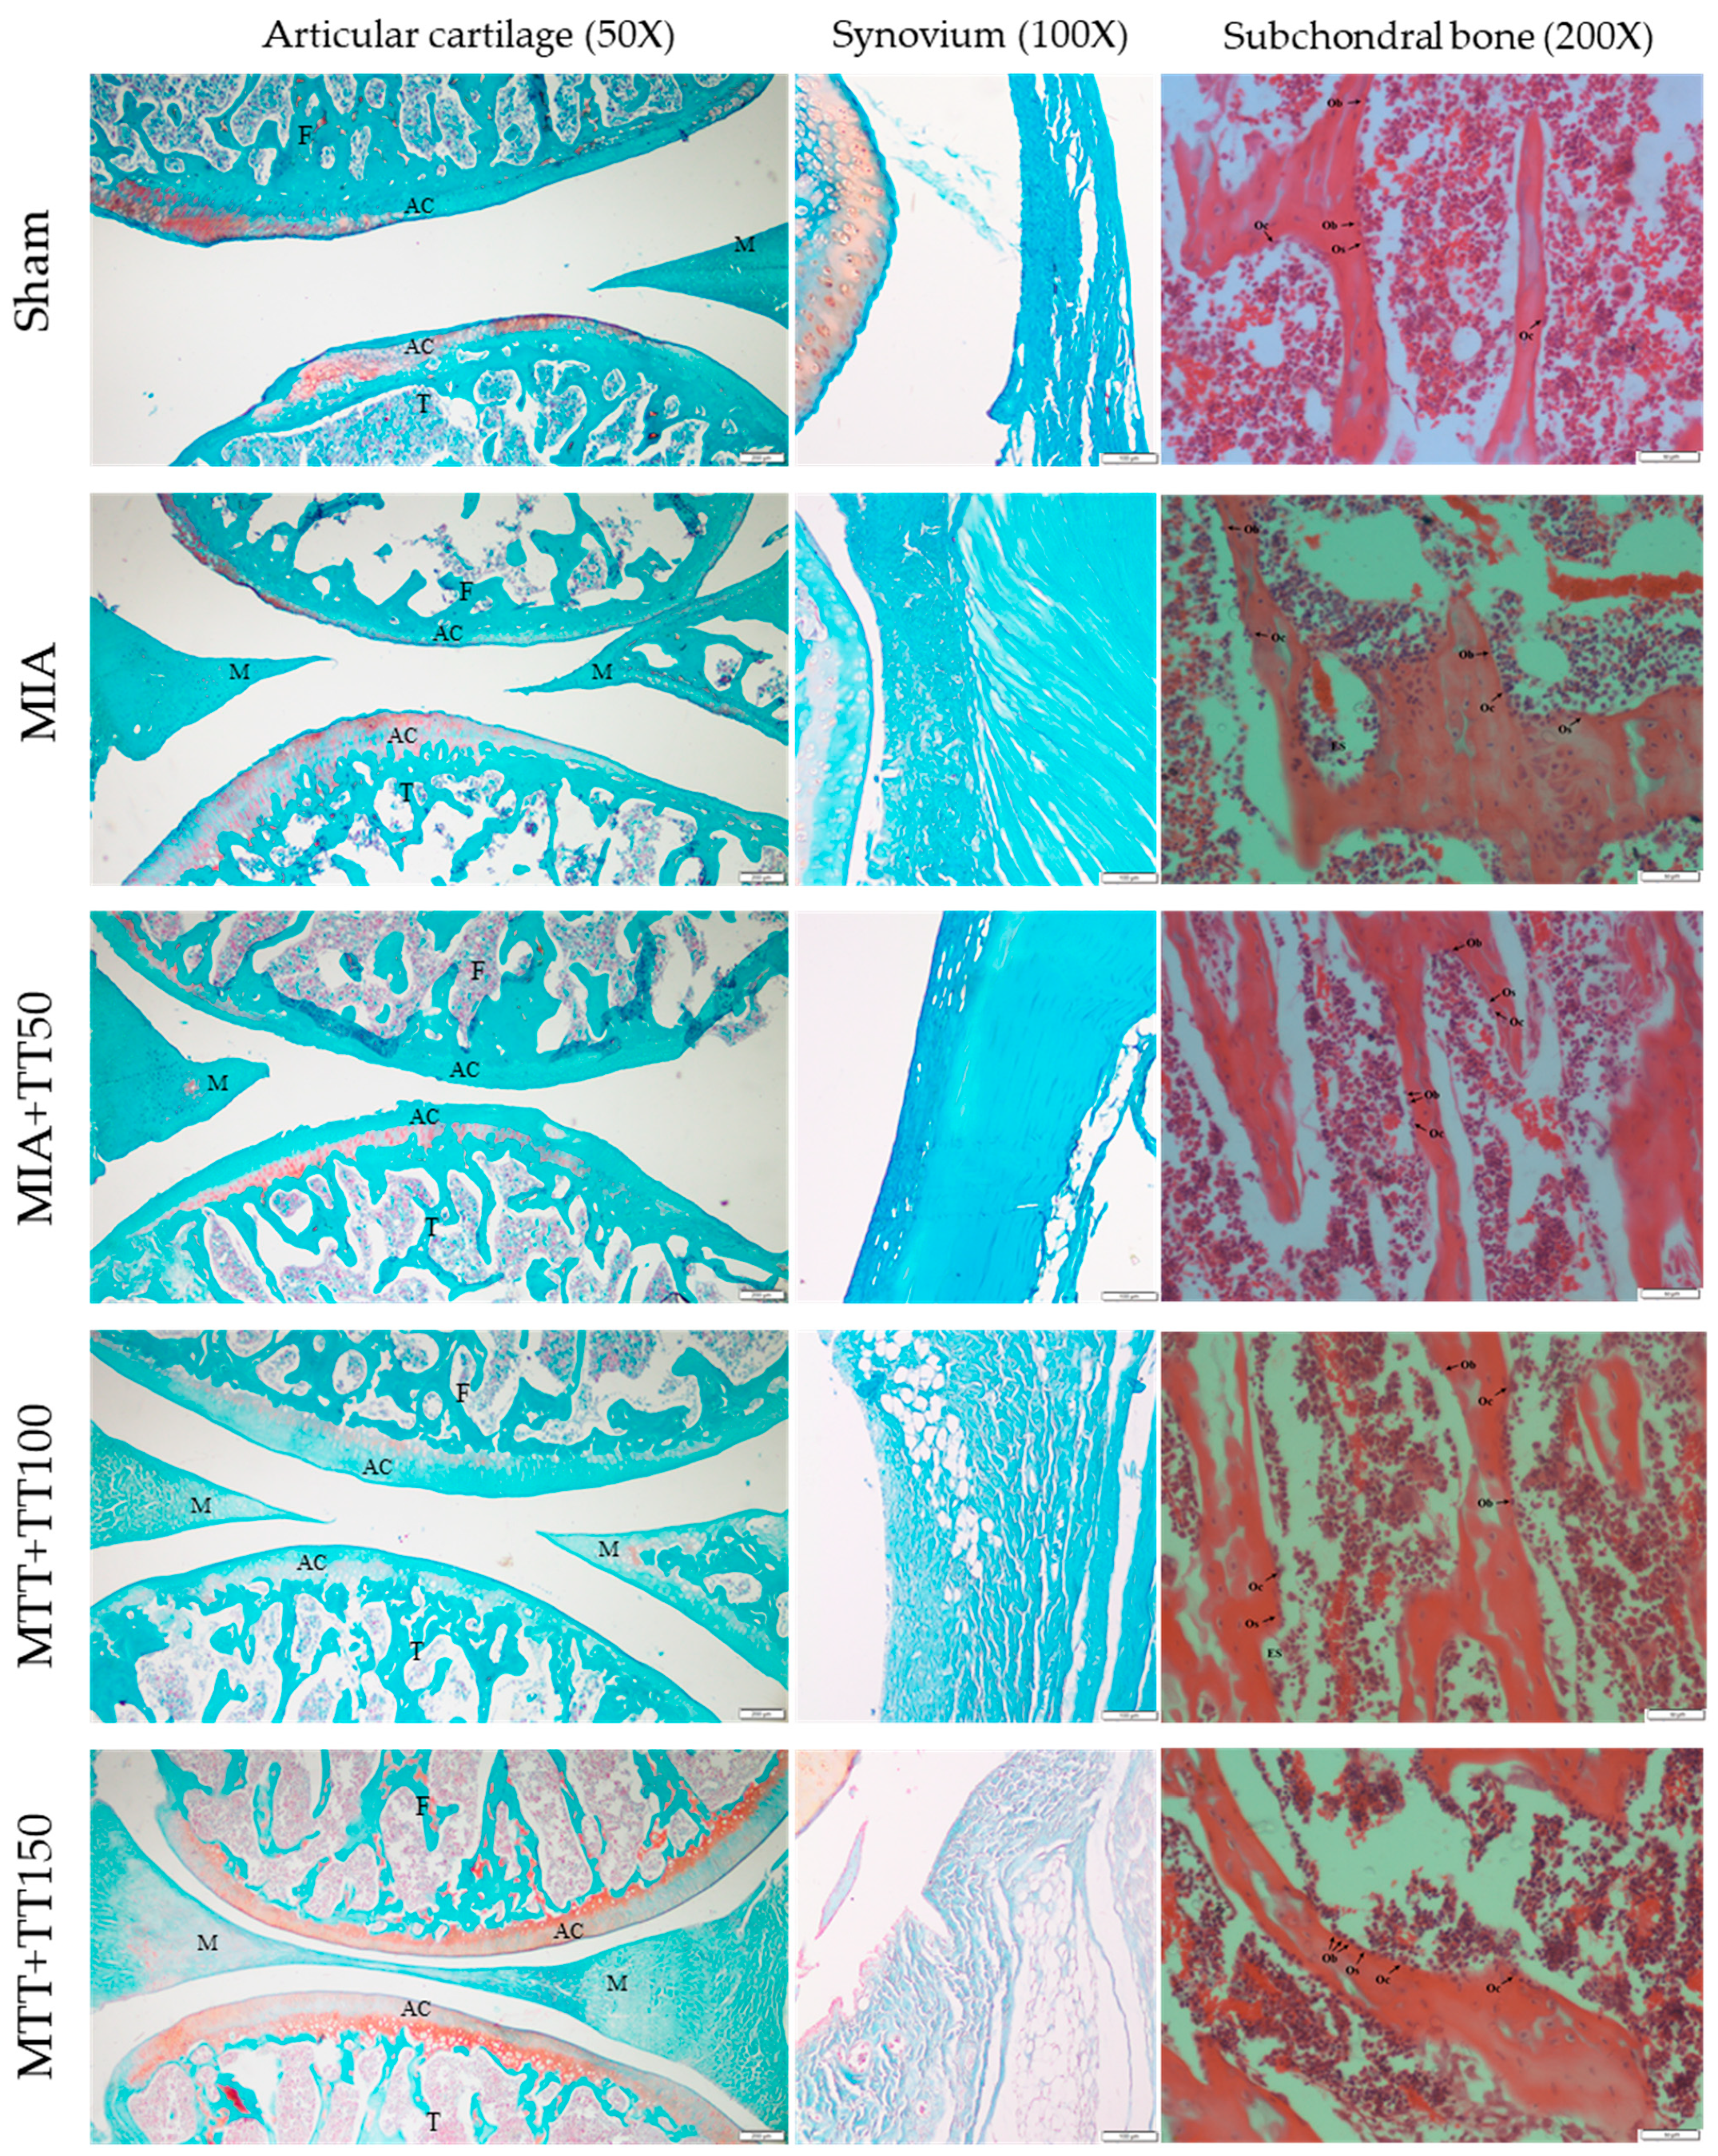

2.3. Histological Analysis

3. Results

4. Discussion